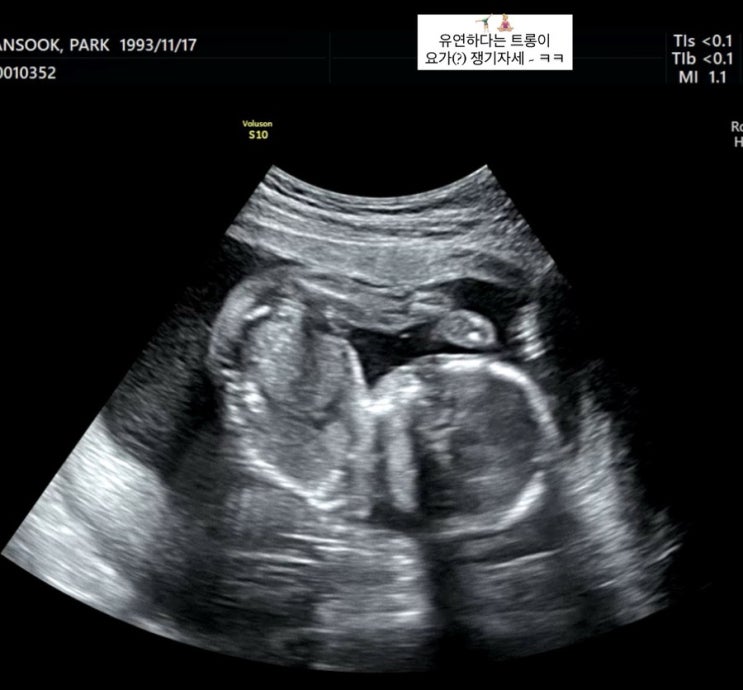

임신일기 : 18주차 ~ 21주차 (임신 중기증상, 첫 태동, 환도선다, 발리 태교여행, 정밀검사 입체초음파, 배뭉침 시작)

?? 나의 트롱이 일지 18주 ~ ?? #18주2일 |2024.03.05 주말부터 갑자기 배에서 뽀로록 거품이...